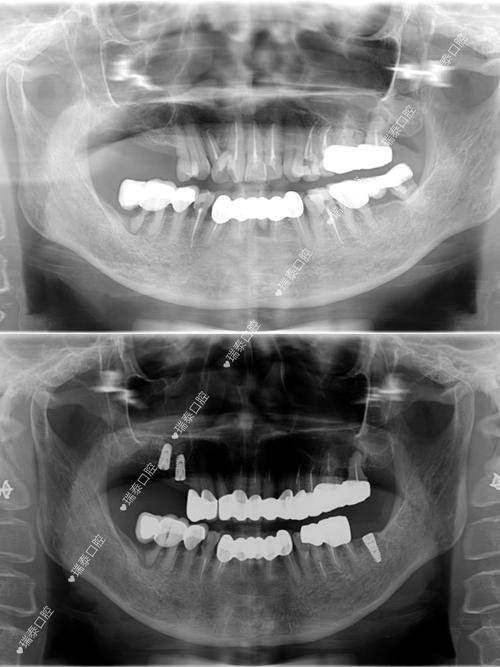

- 影像学检查: 必须拍摄CBCT,精确评估牙槽骨的高度、宽度、密度,以及重要的解剖结构(如下牙槽神经管、上颌窦位置)。